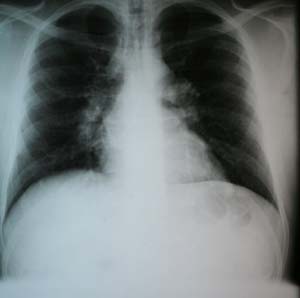

sarcoidosis hilar stage bilateral adenopathy chest lung pulmonary disease lungs lymph radiograph mediastinal node patient thoracic radiography enlargement causes healthy